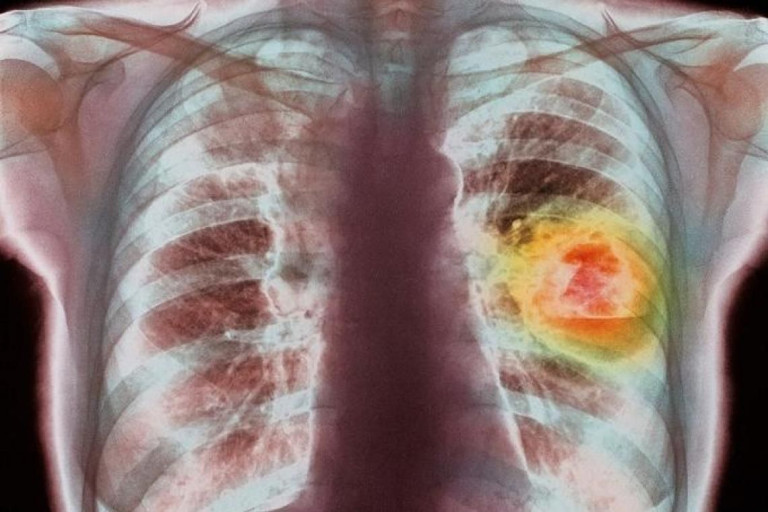

13 พฤศจิกายน 2565 12:14 น. สยามรัฐออนไลน์ คุณภาพชีวิต วันที่ 13 พ.ย.65 เพจ หมอแล็บแพนด้า โพสต์ภาพและข้อความระบุว่า แนวโน้มคนเสียชีวิตด้วยมะเร็งปอด สูงขึ้นทุกปีอย่างต่อเนื่อง ภาคเหนือมากสุด รองลงมาคือกรุงเทพฯครับ ขอบคุณ เพจ หมอแล็บแพนด้า